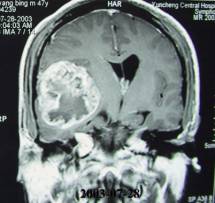

腫瘤高度惡性,高度浸潤性的腫瘤,侵犯破壞周圍腦組織。生長快,病程短,自出現症狀至就診多數在3個月之內。壞死是這類膠質母細胞瘤病理學的標誌,CT上表現為腫瘤中央部位的密度減低區域,周圍為環形異常強化的腫瘤組織。該腫瘤可為原發性,也可由間變型星形細胞瘤進展而來。

4、影像學檢查X線平片、腦血管造影、腦室造影、氣腦造影等均各有其診斷價值。前面已提到,當今診斷顱內腫瘤最理想的輔助檢查是CT和MRI,它們不僅能清晰地顯示腫瘤位置,也能為定性診斷提供重要的信息。